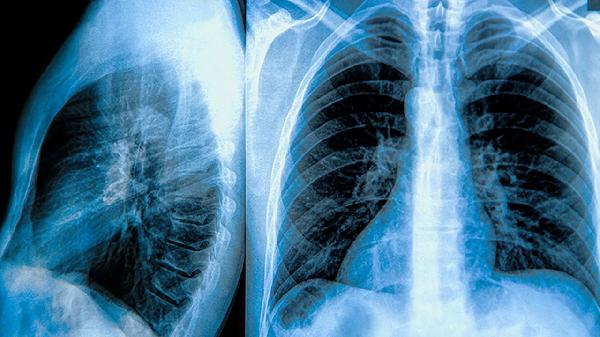

肺气肿肺大泡怎么治疗更有效

肺气肿合并肺大泡的治疗方式主要包括戒烟、使用支气管扩张剂、糖皮质激素治疗、肺减容手术以及肺移植。